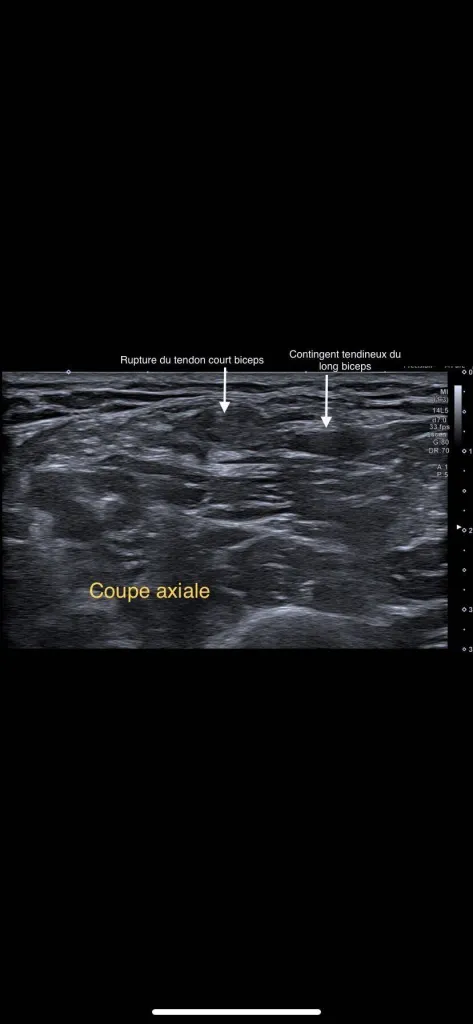

Echographie rue de Lodi : Perte de force de l'avant-bras

Patient venu consulter pour une perte de force en flexion contrarié de l’avant bras avec apparition d’une dépression du galbe au tiers inférieur du bras, sans signe de Popeye associé.L’échographie des muscles et des tendons du bras confirme une interruption des fibres  tendineuses du court biceps ...